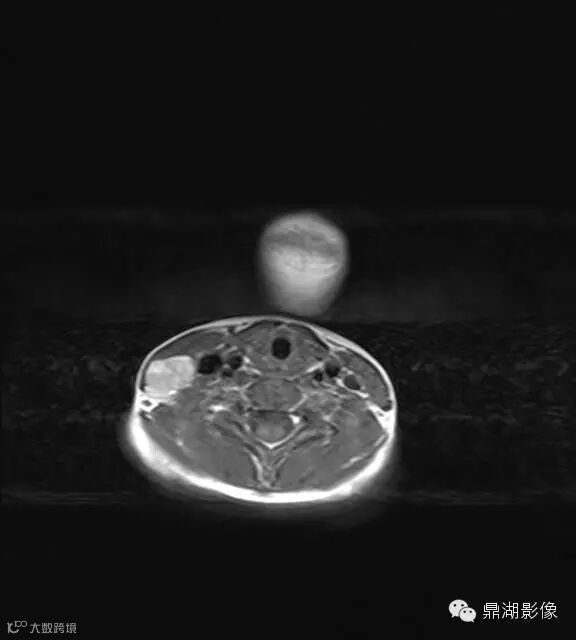

病史:男,5岁,发烧起病 39.5,咽痛,扁桃体II度,家属发现颈部肿块,质地硬,压痛。

上海儿童医院韩燕乔教授诊断:考虑淋巴结炎 ,可见杯状分层,液液平

出院临床诊断:上呼吸道支原体感染,淋巴结炎